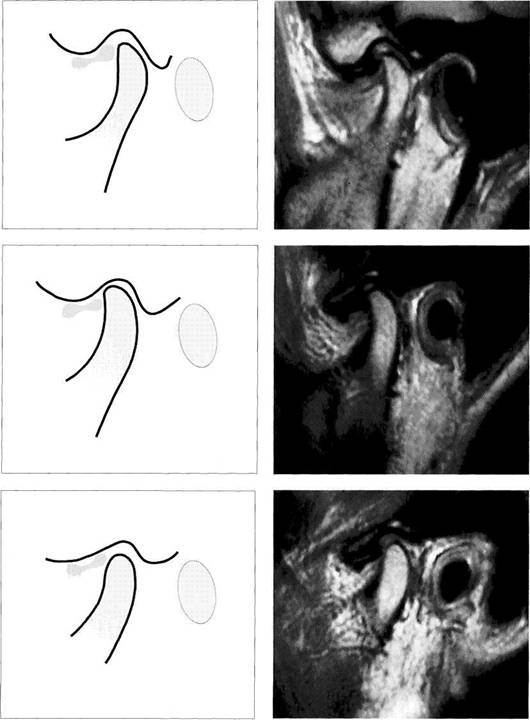

Disk Position in the Sagittal Plane

The disk position with the teeth in habitual occlusion is one of the most important parameters in visual MRI analysis. In the physiological position the disk lies with its pars inter­media in the region of the closest distance between the anterosuperior curvature of the condyle and the articular protuberance. From this position there can be a direct or definite displacement. If the posterior border of the pars posterior lies in front of a line representing the shortest distance between the condyle and the protuberance there is definite disk displacement. With this condyle-disk relation there will always be a clicking sound insofar as the disk can

reposition itself during jaw opening. As long as one part of the pars posterior still lies on the condyle, it is referred to as an insidious disk displacement or a tendency to disk displace­ment. A separate classification of disk position is made for each of the three joint sections (medial, central, and lateral).

Physiological disk position

Under normal conditions, the pars intermedia (*) of the disk lies be­tween the anterosuperior curva­ture of the condyle and the articular protuberance (arrows). The posi­tion of the posterior border of the pars posterior relative to the vertex of the condyle varies according to the inclination of the protuberance and is therefore not a reliable pa­rameter.

The arrows in this schematic draw­ing mark the relative positions of the condyle and the pars interme­dia to one another.

Insidious disk displacement or a tendency to anterior disk displacement

The pars intermedia lies well in front of the shortest distance be­tween condyle and protuberance (arrows), but the pars posterior (1) still lies on the condyle. Clinically, there are no clicking sounds during jaw opening.

Right: Drawing of a joint with a ten­dency to anterior disk displace­ment. The arrows mark the discrep­ancy between pars intermedia and condyle.

Definite disk displacement

Left: Both the pars intermedia (*) and the posterior border of the pars posterior lie in front of the most anterosuperior curvature of the condyle (arrows). Unless this is a case of disk displacement without repositioning, a clicking sound will occur regularly during jaw opening.

Right: Schematic drawing of a defi­nite anterior disk displacement. The arrows mark the discrepancy between the pars intermedia and condyle.